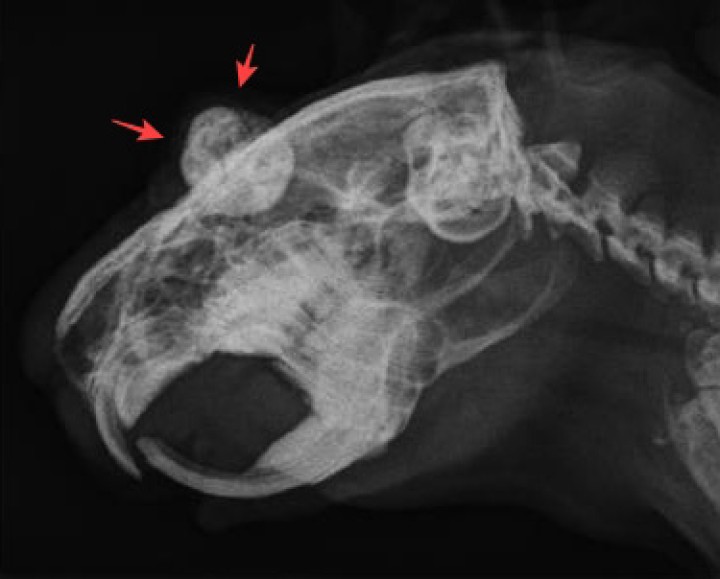

Debido al mal pronóstico de las lesiones en el globo ocular, se decidió realizar la enucleación del mismo. La analítica sanguínea prequirúrgica resultó normal. Se realizaron radiografías de cuerpo entero (sin alteraciones reseñables) y de cráneo, las cuales evidenciaron radiopacidad heterogénea del OD con silueta redondeada irregular (Figs. 4 y 5). El protocolo anestésico consistió en una combinación de midazolam 1 mg/kg IM (Midazolam Normon 15 mg/3ml Solución inyectable, Normon, Madrid), buprenorfina 0,03 mg/kg IM (Buprecare 0,3 mg/ml solución inyectable, Haupt Pharma Livron, Francia), ketamina 3 mg/kg IM (Anesketin 100 mg/ml solución inyectable, Dechra Veterinary Products SLU, Barcelona) y dexmedetomidina 0,05 mg/kg IM (Dexdomitor 0,5 mg/ml solución inyectable, Orion Corporation, Espoo). Se realizó la inducción mediante mascarilla con sevofluorano (Sevoflo 100% líquido, Zoetis, Bélgica) al 4% en oxígeno. El mantenimiento de la anestesia se realizó mediante mascarilla con sevofluorano al 2% en oxígeno. Se llevó a cabo la enucleación del globo ocular mediante el método transconjuntival. El animal se mantuvo estable durante todo el procedimiento quirúrgico y su recuperación postquirúrgica resultó sin complicaciones. Se procedió al alta del paciente con tratamiento ambulatorio consistente en marbofloxacino 5 mg/kg PO q24h durante 10 días (Efex 10 mg comprimidos, Ceva S.A., Barcelona), meloxicam oral 0,5 mg/kg PO q12h durante 7 días, ranitidina 2,5 mg/kg PO q12h durante 7 días (Ranitidina 25 mg/ml, formulación magistral) y alimentación forzada en caso necesario con papilla 10 ml/kg q4-6h (Critical Care Herbivores, Oxbow Animal Health, Omaha, EE.UU.).

<p>Radiografía latero-lateral del cráneo. Se aprecia densidad radiopaca del globo ocular derecho (flechas rojas) compatible con calcificación del mismo.</p>

Figura 5

Radiografía latero-lateral del cráneo. Se aprecia densidad radiopaca del globo ocular derecho (flechas rojas) compatible con calcificación del mismo.